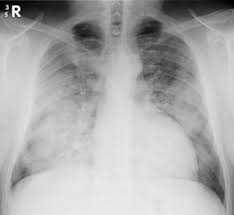

Ards - Formal Guidelines Management Of Acute Respiratory Distress Syndrome Annals Of Intensive Care Full Text : Most people who get ards are already at the hospital for trauma or illness.. Acute respiratory distress syndrome (ards) is a medical condition in which the lungs are not working properly and oxygen blood levels are too low. The american lung association (ala) says ards is a rapidly progressive disease that can occur in critically ill patients—most notably now, in those diagnosed with severe illness resulting from. This month marks the 50th anniversary of the first description of the condition now termed the acute respiratory distress syndrome, or ards. Ards is a type of acute respiratory failure caused by fluid buildup in your lungs. Acute respiratory distress syndrome (ards) occurs when fluid builds up in the tiny, elastic air sacs (alveoli) in your lungs.

Fluid leaks from small blood vessels and collects in tiny. For those who survive, a decreased quality of life is common. Causes may include sepsis, pancreatitis, trauma, pneumonia, and aspiration. Ards is a type of acute respiratory failure caused by fluid buildup in your lungs. But even if they survive, it's a long road to recovery.

This deprives your organs of the oxygen they need to function. On a microscopic level, the disorder is associated with capillary endothelial injury and diffuse alveolar damage. The fluid prevents your lungs from filling with oxygen. Care guide for ards (acute respiratory distress syndrome) (discharge care). The fluid keeps your lungs from filling with enough air, which means less oxygen reaches your bloodstream. Acute respiratory distress syndrome (ards) is a serious lung condition that causes low blood oxygen. People who develop ards often are very ill with another disease or have major injuries. It occurs when fluid fills up the air sacs in your lungs.

On a microscopic level, the disorder is associated with capillary endothelial injury and diffuse alveolar damage. Most people who get ards are already at the hospital for trauma or illness. The outcomes tend to be better in younger patients, trauma patients and when ards is caused by blood transfusions. Acute respiratory distress syndrome (ards) is a condition that causes fluid to build up in your lungs so oxygen can't get to your organs. The american lung association (ala) says ards is a rapidly progressive disease that can occur in critically ill patients—most notably now, in those diagnosed with severe illness resulting from. Most people who develop ards are in the hospital for other serious health problems. In ards, fluid builds up inside the tiny air sacs of the lungs, and surfactant breaks down. The condition causes fluid to accumulate in the lungs, which in turn reduces blood oxygen to dangerously low levels. The diagnosis of ards is based on fulfilling three criteria: Care guide for ards (acute respiratory distress syndrome) (discharge care). People who develop ards are usually ill due to another disease or a major injury. Possible causes, signs and symptoms, standard treatment options and means of care and support. Ards is a medical emergency.

Ards, or acute respiratory distress syndrome, is a lung condition that leads to low oxygen levels in the blood. Covid‐19 ards is a predictable serious complication of covid‐19 that requires early recognition and comprehensive management this disease is still too strange to us, and there are too many doubts, says dr ling qin (lq), after reviewing more than 400 patients with coronavirus disease 2019 (covid‐19) pneumonia in wuhan union hospital, china. In ards, fluid builds up inside the tiny air sacs of the lungs, and surfactant breaks down. Acute respiratory distress syndrome (ards) is a form of acute lung injury and occurs as a result of a severe pulmonary injury that causes alveolar damage heterogeneously throughout the lung. Most people who get ards are already at the hospital for trauma or illness. Causes may include sepsis, pancreatitis, trauma, pneumonia, and aspiration. Ards is a type of acute respiratory failure caused by fluid buildup in your lungs. Acute respiratory distress syndrome (ards) is a medical condition in which the lungs are not working properly and oxygen blood levels are too low.